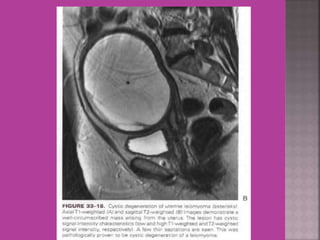

Degeneration Of Fibroid

Cystic Degeneration of

Fibroid

 Myoma—to differentiate myoma from

adenomyoma.localization of myoma—sub

serous/ intra mural or sub mucous.

 Study ofnormal uterus and adnexa – with aim to have clear image of normal myometrium, endometrium , ovary and follicles within the ovary.  Myoma—to differentiate myoma from adenomyoma.localization of myoma—sub serous/ intra mural or sub mucous.  Adenomyosis---accurate diagnosis.  Congenital uterovaginal anomalies— bicornuate, septate,subseptate , unicornuate, didelphys ,rudimentary horn and vaginal atrasia etc